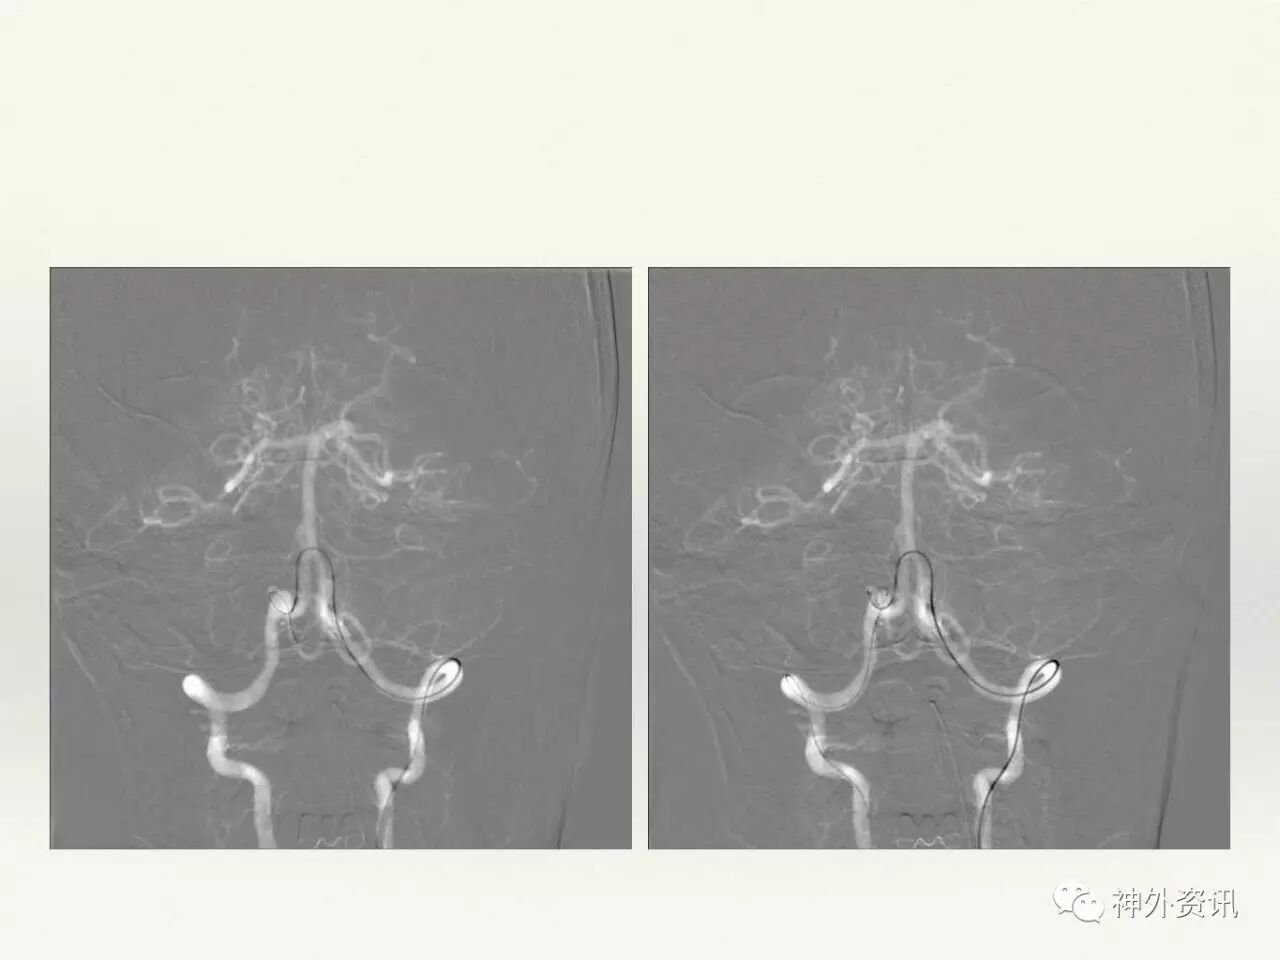

在东北地区率先开展了颈内动脉、大脑中动脉及基底动脉闭塞血管内再通、颅内动脉栓塞急性期取栓、血流导向装置治疗大型宽颈动脉瘤等,对颅内动脉瘤、动静脉畸形、颈动脉及颅内动脉狭窄、颈内动脉海绵窦瘘、硬脑膜动静脉瘘等外科治疗具有较深的造诣。完成脑血管造影8600余例,各类脑血管病介入手术共4500余例,动脉瘤、动静脉畸形、脑肿瘤、脑出血及脑外伤等外科手术1500余例。